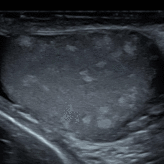

Cowden's syndrome: A case report